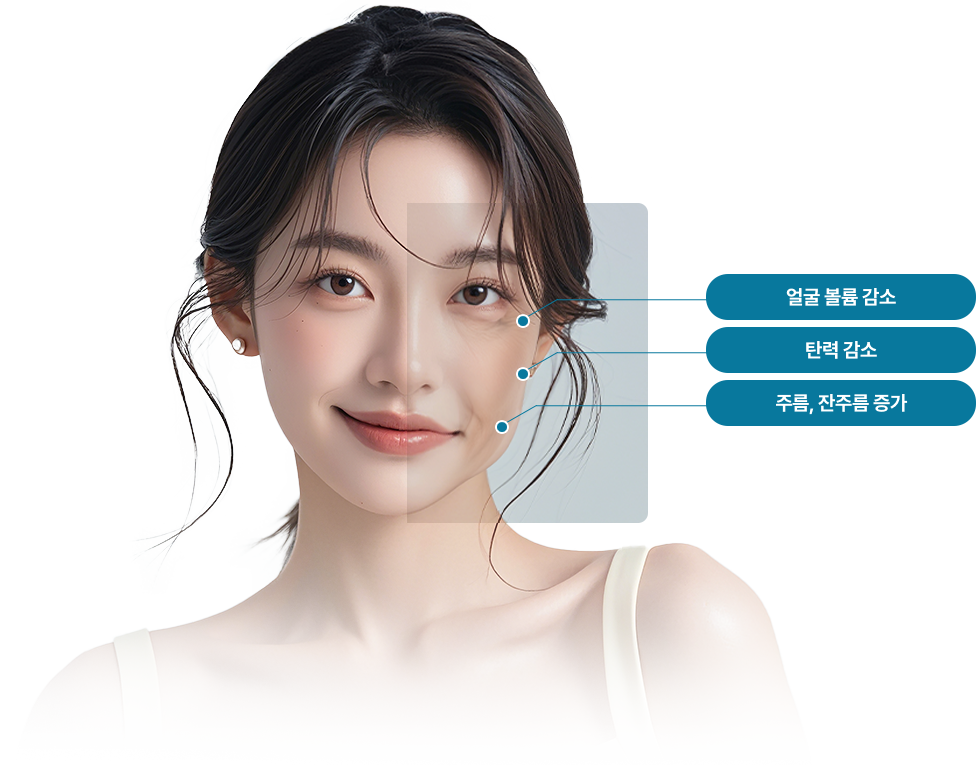

나이가 들수록 피부는 서서히 힘을 잃고, 점점 얇아지며 탄력을 잃게 됩니다.

노화에서 벗어나려면 단순히 겉으로 보이는 결만을 다듬는 케어로는 한계가 있으며

피부 속부터 탄탄하게 채워주는 근본적인 접근이 필요합니다.

노화가 진행되면 섬유아세포와 콜라겐의 활성과 텐션이 감소되어

탄력 감소, 주름, 피부 색변화, 볼륨 감소 등이 발생됩니다.

섬유아세포와 콜라겐의 활성도와 텐션이 점차 감소됨

탄력감소, 주름증가, 볼륨이 감소된 피부